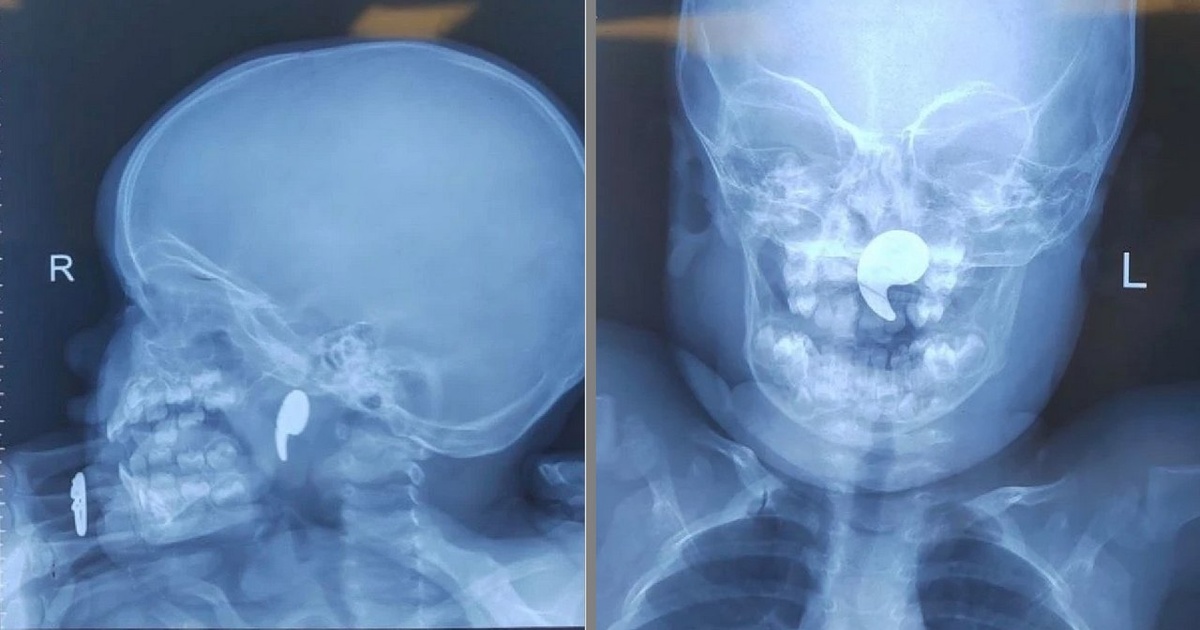

В Воронеже врачи областной детской больницы №1 успешно извлекли магнит из носоглотки полуторагодовалой девочки. Малышка поступила в больницу с жалобами на боль в горле, она отказывалась от еды и у неё было обильное слюноотделение. По словам родителей, малышка играла магнитом в форме запятой. Мать попыталась самостоятельно извлечь инородный предмет из носа дочки, однако тот сместился в носоглотку. Дежурный ЛОР-врач Марина Перепечена провела операцию под общей анестезией с использованием эндоскопического оборудования. Магнит в итоге был успешно извлечён. Через сутки состояние девочки стабилизировалось, и она была выписана под наблюдение педиатра.